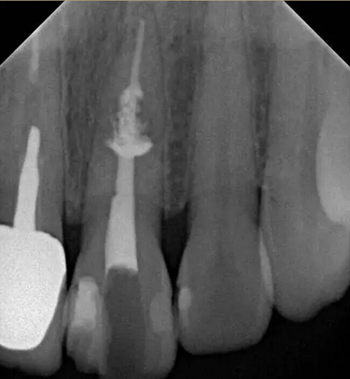

診斷:左上中切牙牙根內(nèi)吸收。治療計(jì)劃:左上中切牙根管治療,全冠修復(fù)。 治療過程:患者知情同意。使用含1/100,000腎上腺素的4%鹽酸阿替卡因(碧蘭麻,艾龍)局部浸潤(rùn)麻醉,橡皮障隔濕。去腐未盡露髓,露髓孔出血多。開髓,使用10#不銹鋼K銼(MANI,日本)探查根管,根管中段有鈣化物阻擋,不能達(dá)到牙根全長(zhǎng)(圖3A)。在顯微鏡下(Leica M400E,萊卡, 德國(guó)) 使用超聲尖(E1根管治療超聲尖,啄木鳥公司,中國(guó))通開,采用根管長(zhǎng)度測(cè)量?jī)x(Root ZX, Morita公司,日本)加診斷絲片法(圖1B)測(cè)量根管長(zhǎng)22 mm。使用控制扭矩馬達(dá)(X-smart,登士柏)和鎳鈦旋轉(zhuǎn)器械(Hero 642, Micromega)根管預(yù)備,根管預(yù)備過程中使用5.25%次氯酸鈉溶液沖洗。 根備完成后使用超聲蕩洗根管,5.25%次氯酸鈉溶液3 分鐘, 17% EDTA溶液1分鐘。干燥根管,使用螺旋充填器根管內(nèi)封氫氧化鈣糊,氧化鋅丁香油水門汀暫封。1周后患者復(fù)診,患者述無術(shù)后不適,檢查暫封完好,無叩痛,不松,牙齦無紅腫瘺管。使用橡皮障隔濕,去除暫封物,超聲蕩洗根管,5.25%次氯酸鈉溶液3 分鐘, 17% EDTA溶液1分鐘。干燥根管,牙膠尖(達(dá)雅鼎,中國(guó))和必蘭根充糊劑(Cortisomol, 艾龍公司,法國(guó))熱垂直加壓法根管充填。術(shù)后片顯示根充恰填,可見牙膠/糊劑被壓入鈣化物周圍和內(nèi)部縫隙內(nèi)